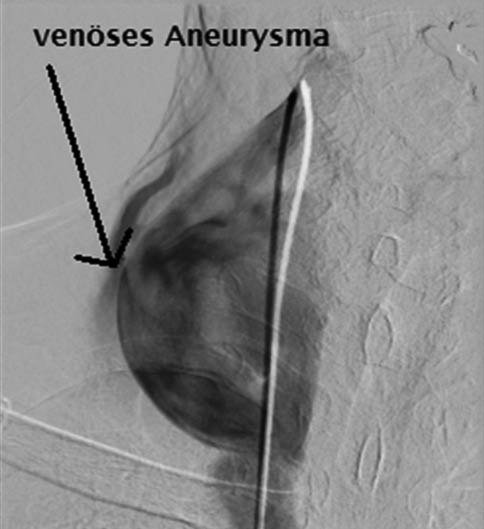

Abb. 4: MR-Angiografie

(koronare Projektion) – betonte Intercostalarterien